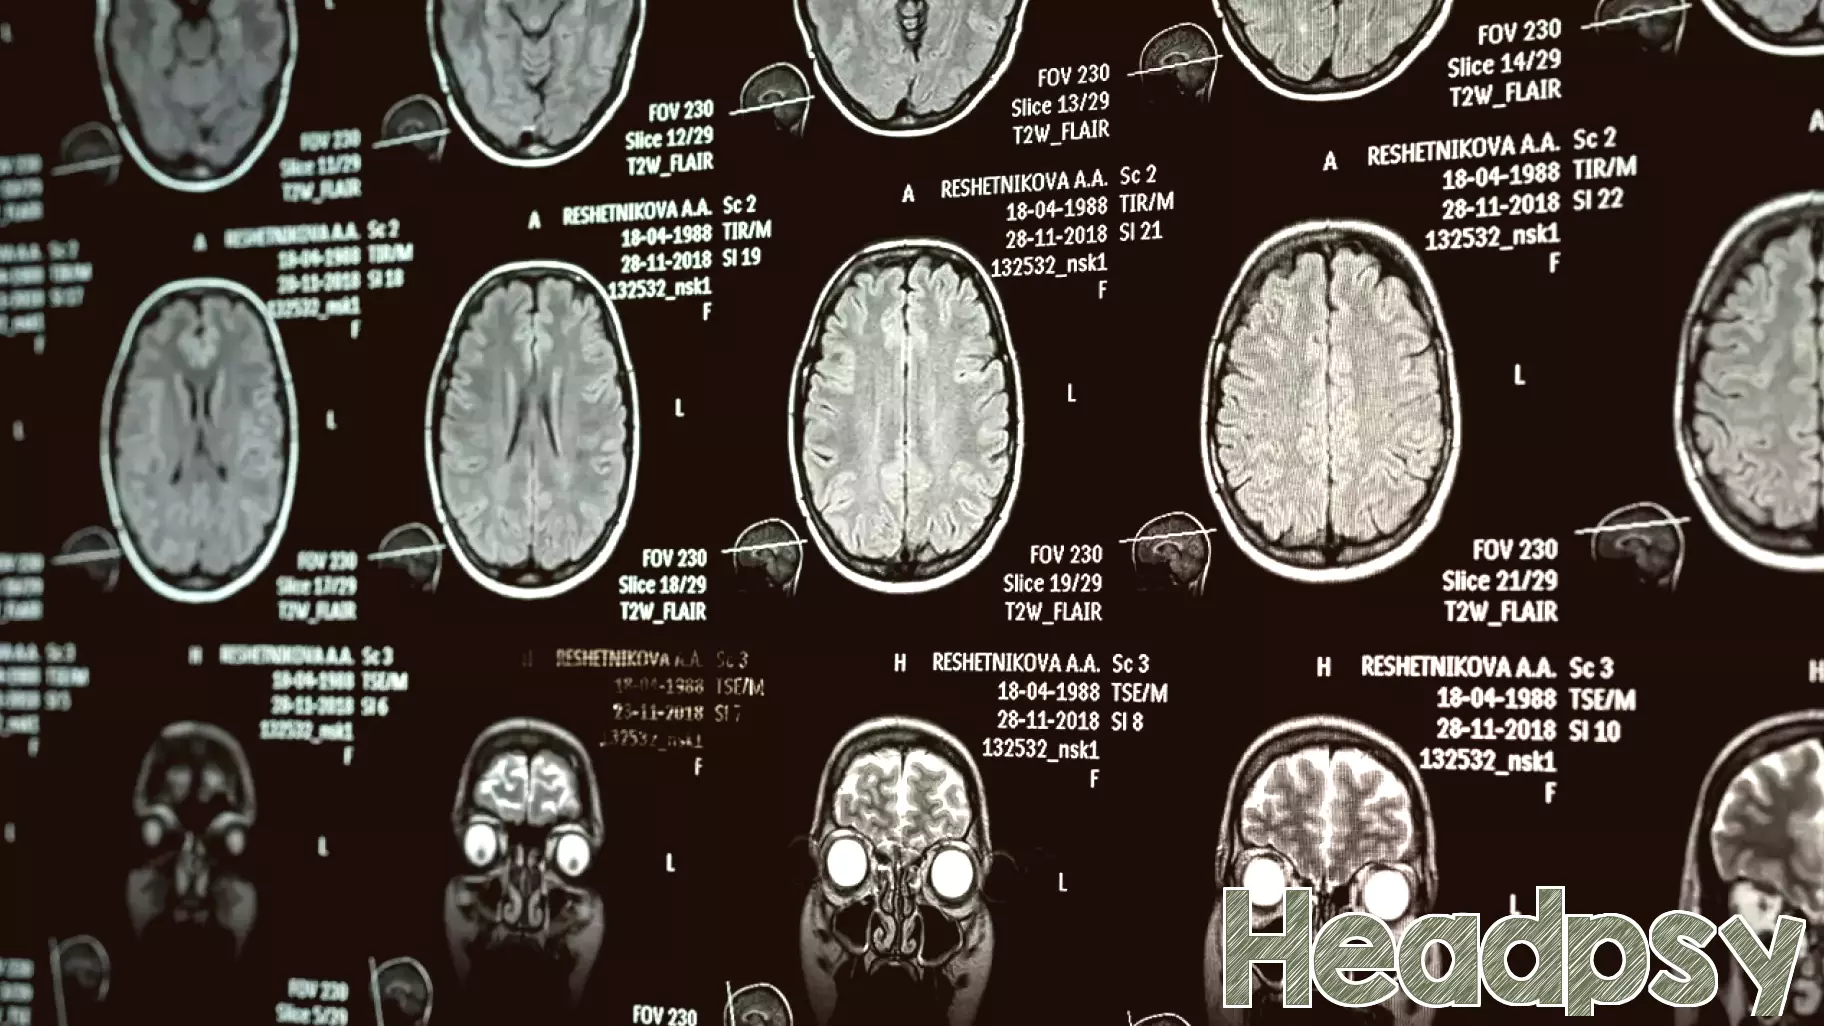

A new brain imaging study reveals a direct neurological link between narcissistic personality traits and the common tendency to suppress emotions. The research focused on a deep-seated brain region known as the anterior insula, a critical hub for self-awareness and emotional control.

Scientists discovered that individuals scoring higher in narcissism, particularly in traits related to entitlement and self-centeredness, had a distinct physical structure in this area. Their anterior insula exhibited a thicker cortex and altered connectivity patterns. This specific brain profile was strongly associated with a greater habitual use of expressive suppression—the act of concealing or inhibiting emotional expressions.

The findings suggest that the very brain machinery governing our emotional experience is structurally different in people with pronounced narcissistic traits. This neurological signature may underpin their frequent use of emotional suppression as a regulatory strategy, potentially to maintain a specific self-image or to manipulate social interactions. The study provides a rare biological insight into the complex interplay between personality, emotion regulation, and brain anatomy, moving beyond purely behavioral observations.